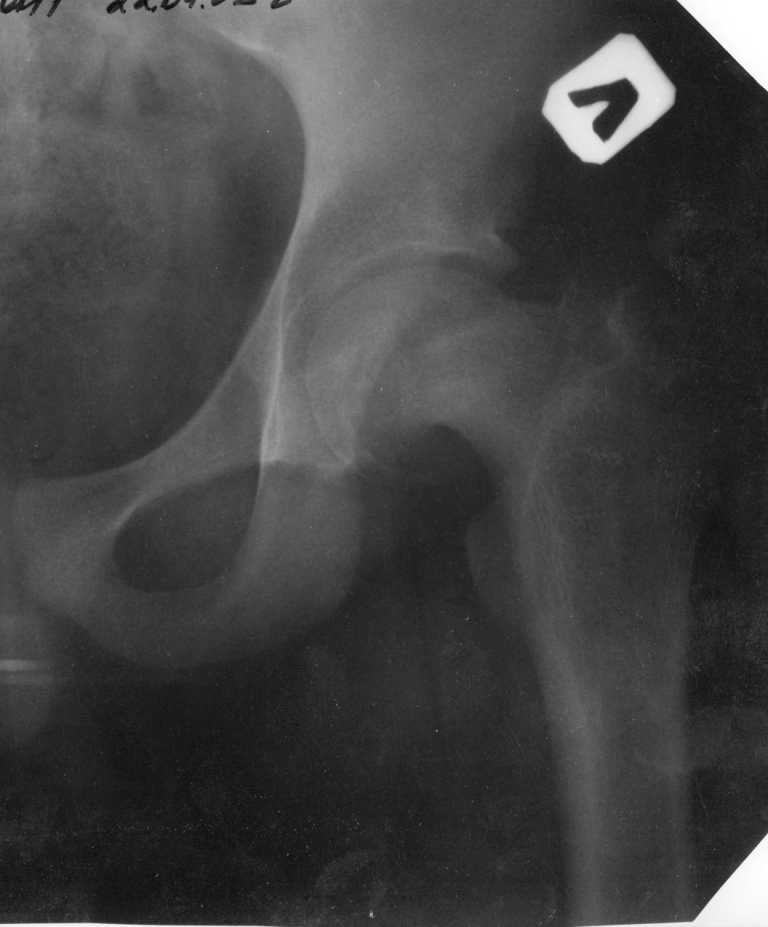

Ребёнок 14 лет. Весом под центнер. Имеющаяся рентгенологическая деформация деформация - на момент поступления. Госпитализирован ребёнок 14 лет. Мальчик, мягко говоря, крупный, гиперстенического типа сложения, ближе к десантнику. Весит 95 кг. Ожирение 2-й степени. Со слов больного - испытывает дискомфорт в области тазобедренного сустава в течение 3-х месяцев. На рентгенограммах - положение дел на момент поступления - конец мая. Укорочение конечности на 1,5 см. Ограничение внутренней ротации. Ходит, едва заметно прихрамывая на больную ногу. Эндокринологический статус находится в стадии обследования. Выполнена рентгенография в стандартных укладках, спиральная КТГ.Ясное дело, головка бедра <ушла> вниз и кзади. Пытающаяся <поймать> её шейка варизировалась и исполнила ретроверсию, создав изгиб во фронтальной плоскости. На рентгеноскопии - подвижность головки не определяется. Мальчик имеет далеко идущие планы на обустройство собственной жизни и образование. Крайне негативно относится к длительной иммобилизации и консервативному лечению. Загодя не согласен со снижением качества жизни в процессе лечения. Мнения коллег относительно дальнейшего лечения разделились. Успешность репозиции головки под наркозом - сомнительная в связи с имеющейся деформацией шейки бедра. Одни склоняются к тактике невмешательства - разгрузка больной конечности, ФЗТ , массаж, и т.д. Предлагают ждать завершения процесса <сползания> головки в условиях полной разгрузки, <тянуть> сустав до эндопротезирования как можно дольше. Другая группа коллег предлагает немедленную стабилизацию головки, что, кажется, правильно. Принимая во внимание анатомическое соотношение головки и шейки бедра, способ остеосинтеза так же вызвал массу споров, не приведших к единому и окончательному мнению. Пока дискуссия остановилась на стабилизации спицами Бека под контролем ЭОП, возможно с применением электродов для проведения электростимуляции слабыми импульсными токами. Техника проведения спиц, однозначно, будет сопряжена с техническими трудностями, обусловленными имеющейся деформацией шейки. Как бы Вы поступили, коллеги, в данной ситуации?Заранее спасибо. И прошу прощения за качество спимков. Буду отправлять их по очереди.

Второй сустав пока нормальный, но,каюсь, не прав, надо было не обрезать снимок. Исправлю.